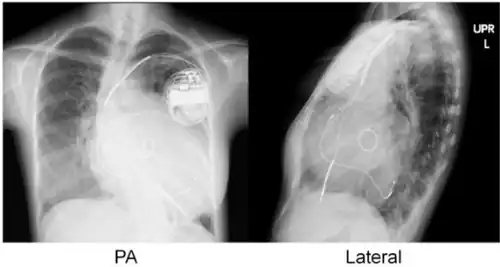

Implanted cardiac resynchronization device | |

Cardiac resynchronisation therapy (CRT or CRT-P) is the insertion of electrodes in the left and right ventricles of the heart, as well as on occasion the right atrium, to treat heart failure by coordinating the function of the left and right ventricles via a pacemaker, a small device inserted into the anterior chest wall.[1]

CRT requires the placement of an electrical device for biventricular pacing, along with placement of (at least) two pacing leads, to facilitate stable left ventricular and right ventricular pacing. For all elements, the first stage of the process is local anaesthetic followed by incision to allow for approach from the appropriate vein. From here, the leads and device can be inserted.[1]

The device is inserted in a subcutaneous pocket created by the surgeon, the choice of left or right side of the chest wall is determined mainly by the patient's preference or location of preexisting device. The device, similar to that of a traditional pacemaker, is generally no larger than a pocket watch and has inserts for the electrode leads.[1]